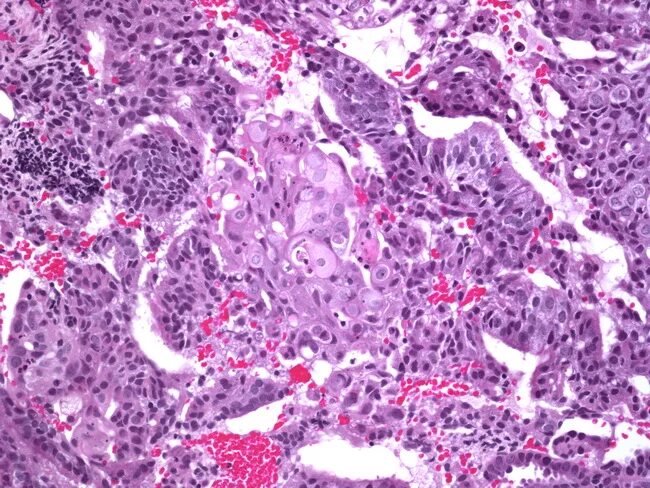

Гистология при раке